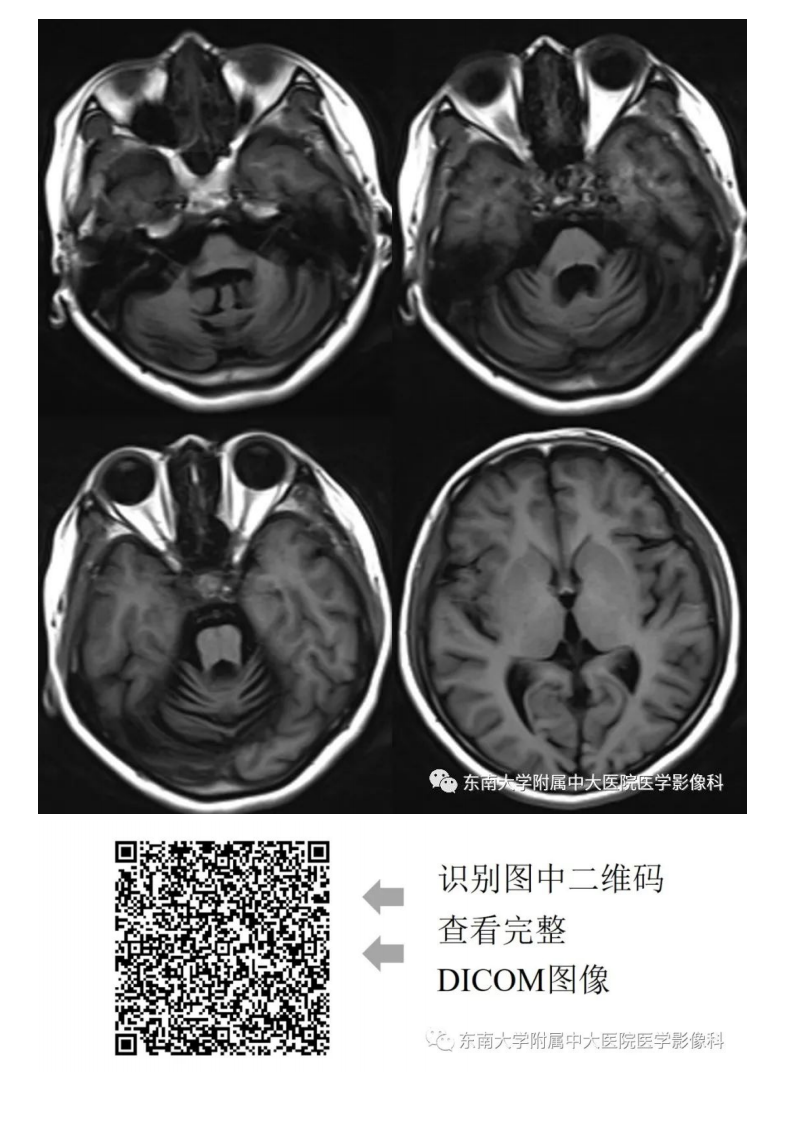

20200928_2【晨读结果公布】2020.09.28神经系统疾病——脊髓小脑性共济失调(病例1).pdf